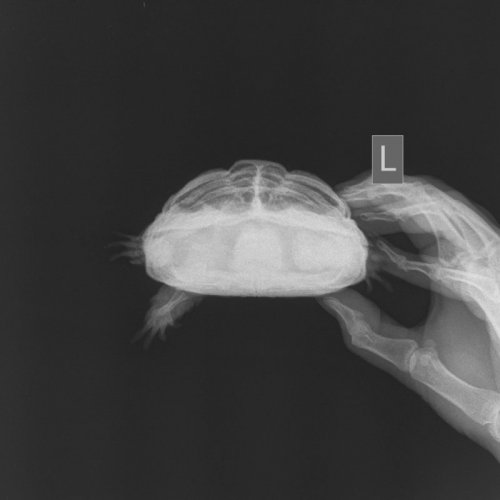

strawberrymilk Ваше имя: Дарья Локация: Пенза Опубликовано: 2 октября 2020 Автор Опубликовано: 2 октября 2020 @moth Съездили в вет. клинику на рентген. Ветеринар сказал, что у неё есть лёгочная недостаточность из-з продавленных 2 пластин. Вес черепах: 0.56, 0.48 и 0.42 кг.

Консультанты moth Ваше имя: Мария Локация: Москва Опубликовано: 2 октября 2020 Консультанты Опубликовано: 2 октября 2020 @victoria146 в Воронеже есть герпетолог Татьяна Волкова https://vk.com/vetpomoshvrn. Я не знаю на сколько она квалифицированный врач, но по постам в ВК я не нашла ничего плохого или сильно неправильного от неё. Думаю рентген она точно сможет сделать. Но вообще рентген с контрастом делают только при подозрении на непроходимость. Всё остальное можно посмотреть просто так, главное в правильной проекции и чтобы оборудование было хорошее. @strawberrymilk по снимкам врач увидел фолликулы увеличенные, они давят на другие органы. Нужно колоть кальций, Элеовит, делать вибротерапию. У самки какой вес?